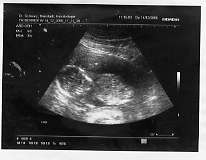

16.11.06